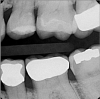

Fig. 2. A radiographic view of the extensive carious lesion on the distal of tooth No. 13.

Figure 2